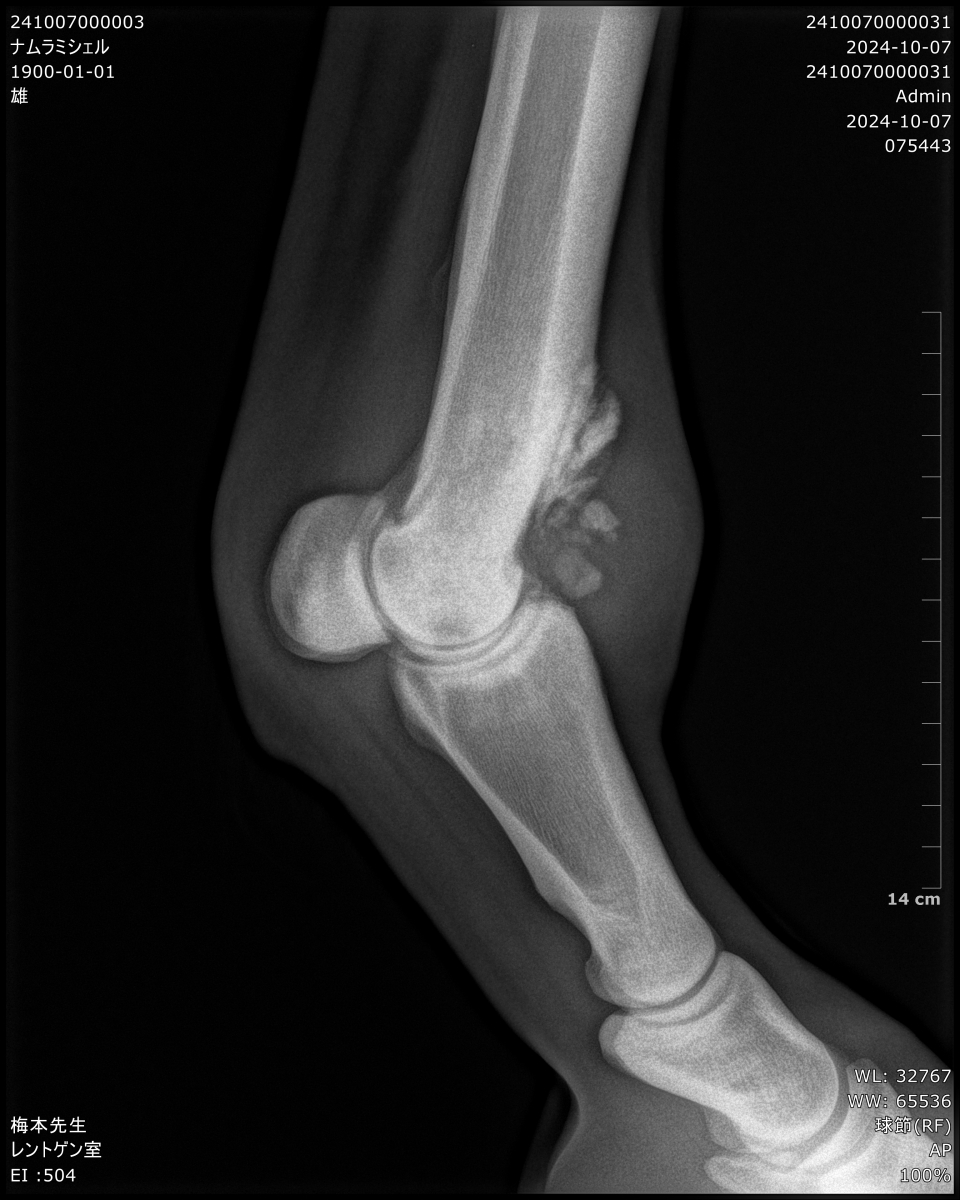

・2024/10/07 入厩前の放牧先である茨城・ケイワンステーブルにて歩様が乱れたためレントゲン検査を行ったところ、以前より腫れを指摘されていた右前の球節部分に骨膜が出ていることが確認。骨膜が大きく出ており、治療を行ったとしても復帰までには相応の時間がかかることから、10/10のサラオクに出品することで共有馬主間で合意。